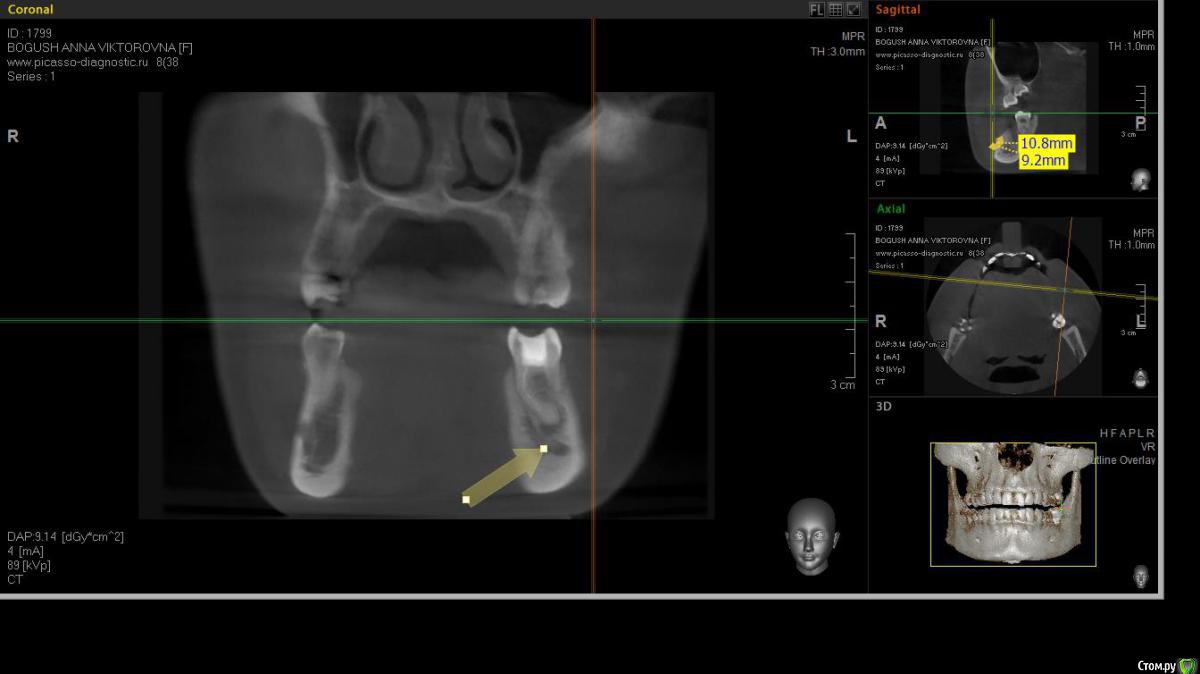

cor Опубликовано 2 апреля, 2016 Поделиться Опубликовано 2 апреля, 2016 Доброго времени суток, коллеги! Каков Ваш прогноз? Удалять пац. совсем не хочет(знакомая). Есть хоть какая то вероятность, что ретрит поможет? <script> </script> Ссылка на комментарий

cor Опубликовано 2 апреля, 2016 Поделиться Опубликовано 2 апреля, 2016 (изменено) гадская вирусятина на компе мешает. Нет конечно желающих. Но если ретрит будет, то делать его буду я. Но слабо верю в положительный исход(( Изменено 2 апреля, 2016 пользователем cor Ссылка на комментарий

Гарриевич Опубликовано 3 апреля, 2016 Поделиться Опубликовано 3 апреля, 2016 Доброго времени суток, коллеги! Каков Ваш прогноз? Удалять пац. совсем не хочет(знакомая). Есть хоть какая то вероятность, что ретрит поможет? шансов не меньше чем тут Ссылка на комментарий

St. Опубликовано 3 апреля, 2016 Поделиться Опубликовано 3 апреля, 2016 Доброго времени суток, коллеги! Каков Ваш прогноз? Удалять пац. совсем не хочет(знакомая). Есть хоть какая то вероятность, что ретрит поможет? Вполне есть смысл попробовать. Вероятность есть, только "заживать" будет долго. Ссылка на комментарий

cor Опубликовано 5 апреля, 2016 Поделиться Опубликовано 5 апреля, 2016 Почему?Наверное потому что такие объемные очаги ещё не перилечивал. Но деваться некуда, будем пробовать. Ссылка на комментарий

Л Ю С Я Опубликовано 5 апреля, 2016 Поделиться Опубликовано 5 апреля, 2016 Наверное потому что такие объемные очаги ещё не перилечивал. Но деваться некуда, будем пробовать.Уже не раз писали, что размер не имеет значения)))). Не надо перелечивать очаг. Ваша задача пройти, правильно сформировать, очистить и запаковать каналы, а также правильно восстановить коронковую часть. И будет вам хилинг))) 2 Ссылка на комментарий